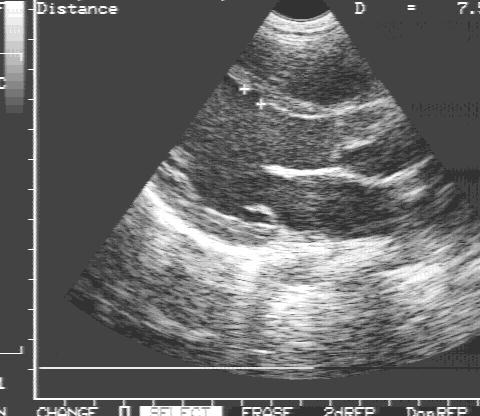

Одномерная ЭхоКГ:

1. Объемная перегрузка правого желудочка (дилатация правых отделов сердца, парадоксальное движение межжелудочковой перегородки) (рис.77).

Частично открытый атриовентрикулярный канал.

Рис.77

Частично открытый

атриовентрикулярный

канал в одномерном

эхоКГ, объемная

перегрузка правого

желудочка.

Парадоксальное дви-

жение МЖП,

тип А.